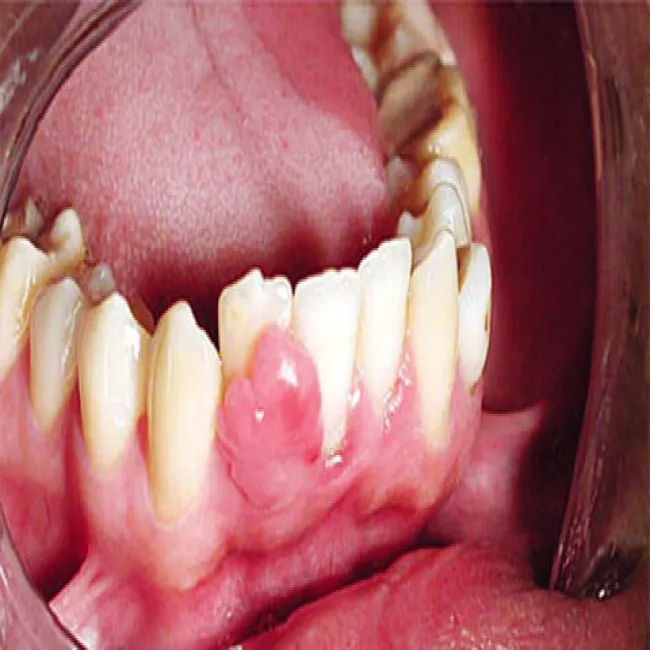

Narośl na dziąśle przy zębie nadziąślak

Nadziąślak, epulis

Nadziąślak

Jama ustna